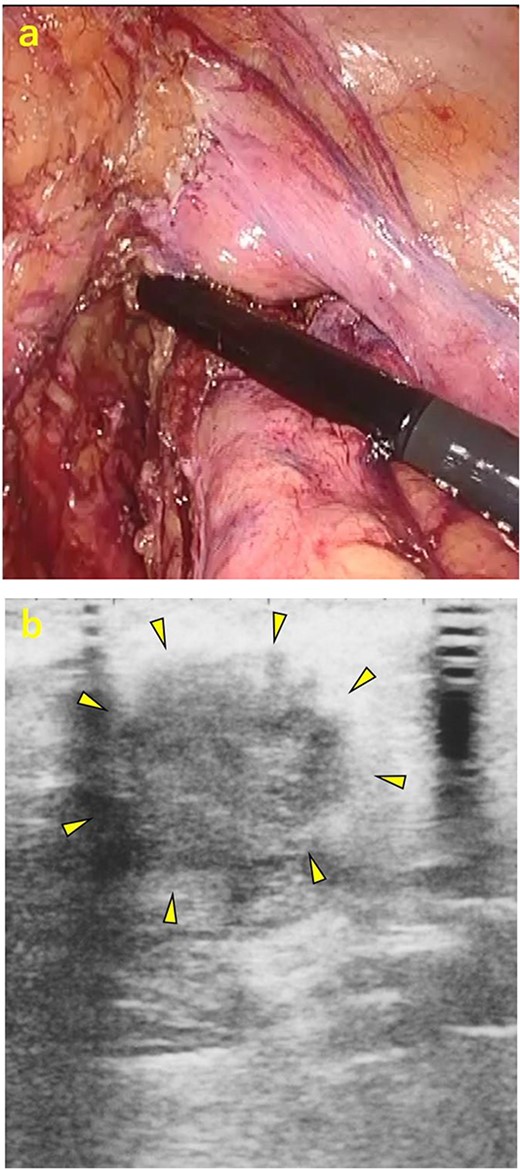

A 70-year-old man was referred to our urology department for prostate cancer based on a mass contiguous with the rectum seen on an imaging scan. He had a Gleason score of 4 + 5, seminal vesicle invasion, and pelvic lymph node metastasis. A month of combined androgen blockade therapy had reduced his prostate-specific antigen (PSA) levels from 25.29 to 10.81 ng/ml. He was diagnosed with rectal cancer at 68 years old and had undergone an endoscopic mucosal resection (EMR) and curative resection. The tumor marker levels were as follows: carcinoembryonic antigen, 2.8 ng/ml and carbohydrate antigen 19–9, 25.4 U/ml. Lower gastrointestinal endoscopy revealed only an EMR scar in the rectum. Computed tomography (CT) revealed a 20-mm large extramural growth-type mass on the left wall of the rectum, 9 cm from the anal verge (Fig. 1a). The mass had a weak enhancing effect and somewhat irregular limbus, and was continuous with the rectus muscularis. The mass was close to the ureter-hypogastric fascia and was suspected to have invaded the pelvic plexus. We observed an enhancing effect in the left lobe of the prostate, and an enlarged left lateral lymph node. No distant metastases were found in other organs, including the bones. Magnetic resonance imaging (MRI) revealed that the mass may have originated from the muscularis propria of the rectum (Fig. 1b). The prostate carcinoma partially touched the rectum beyond the capsule, with no evidence of invasion. 18F-fluorodeoxyglucose-positron emission tomography-CT (FDG PET-CT) showed accumulation in the mass, with a maximum standardized uptake value of 5.96. There was no accumulation in any other organ, including the prostate and pelvic lymph nodes (Fig. 1c). After examination, gastrointestinal stromal tumor (GIST), neuroendocrine tumor (NET), and lymph node metastatic recurrence of rectal cancer were considered as differential diagnoses. Endoscopic ultrasound-guided fine needle aspiration (EUS-FNA) was scheduled for pathological diagnosis. However, since the patient denied the EUS-FNA and preferred an early resection, we performed only surgery. During the laparoscopic low anterior resection, a laparoscopic ultrasonography probe was applied to the mesorectum to identify the mass (Fig. 2a). A hypoechoic area was observed in the left mesorectum (Fig. 2b). Since we suspected invasion into the ureter-hypogastric fascia, the area around the lesion was resected, with partial merging of the pelvic plexus. Postoperatively, the patient had a mildly relieved neurogenic bladder and was discharged on postoperative Day 8. The resected specimen showed a well-defined 18 × 16 mm large borderline mass predominantly on the lower rectal adventitia (Fig. 3a). The lesion was non-contiguous and located contralateral to the EMR scar. Histopathological findings revealed that the mass was poorly differentiated carcinoma and grew to compress the muscularis propria (Fig. 3b). The tumor was immunohistochemically positive for CK AE1/AE3 and NKX3.1 (Fig. 4a); partially positive for PSA (Fig. 4b); and negative for CK7, CK20, CDX2 (Fig. 4c), TTF1, chromogranin A, synaptophysin, CD56, C-KIT, and SOX10. Therefore, the tumor was diagnosed with rectal metastasis of prostate cancer. Cancer metastases of similar histology were also found in other resected lymph nodes. Enzalutamide was started 2 months postoperatively, but due to tumor and metastatic lymph node enlargement, docetaxel treatment was started at 5 months postoperatively. However, the disease continued to progress, and he died 10 months after surgery.

Intraoperative ultrasonography. (a) A laparoscopic ultrasonography probe was applied to the mesorectum to identify the mass. (b) A hypoechoic area of ~20 mm